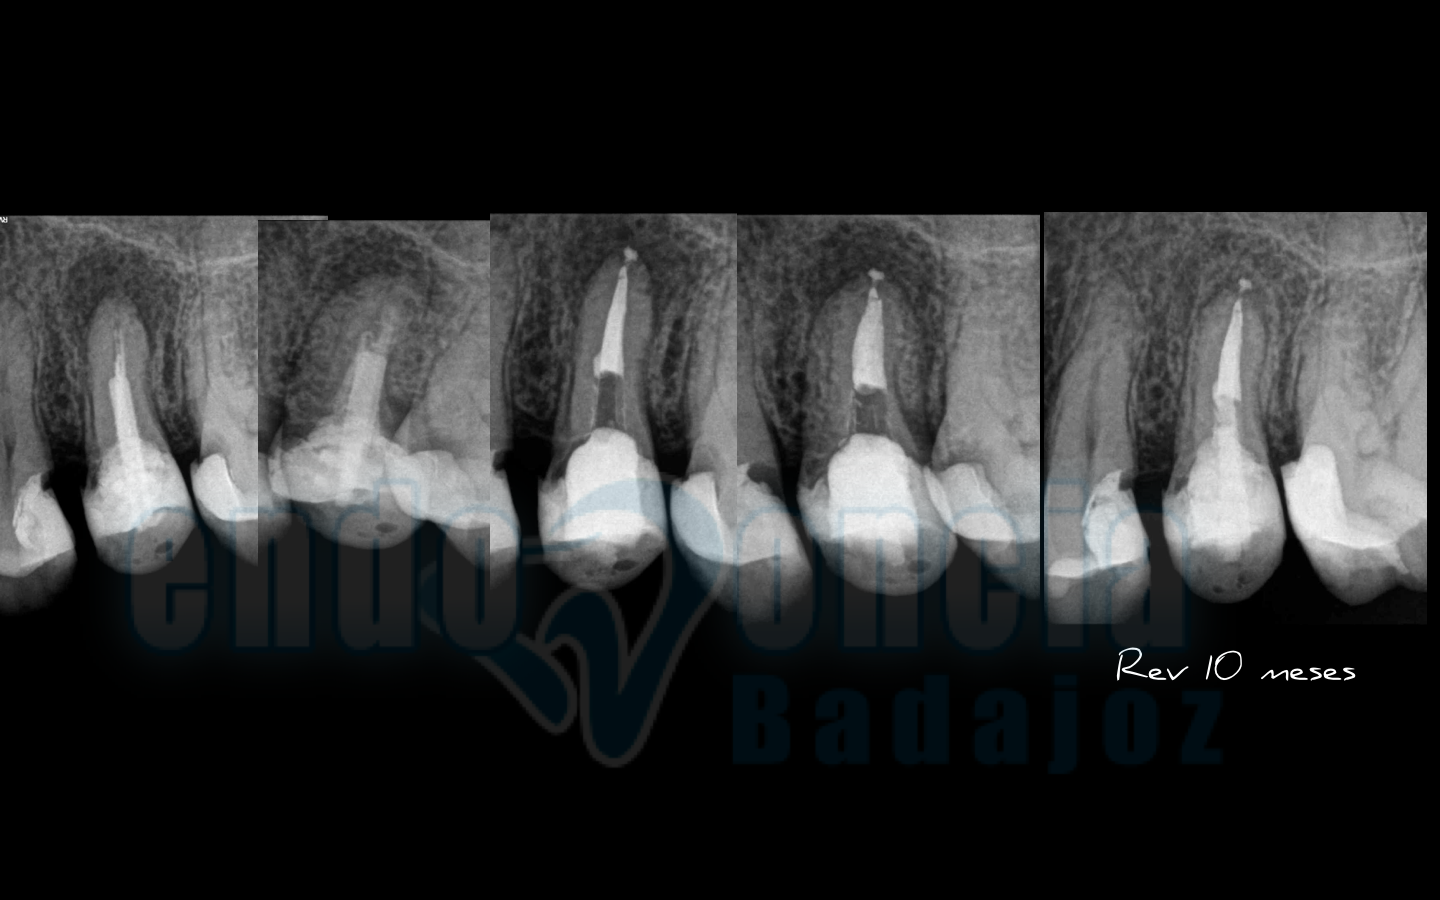

Caso 3:

Molar inferior , con una Periodontitis Apical Asintomática, con gran lesión apical, que vemos que manejando la anatomía interna y haciendo un buen tratamiento, a los 10 meses vemos una gran regeneración de la lesión.